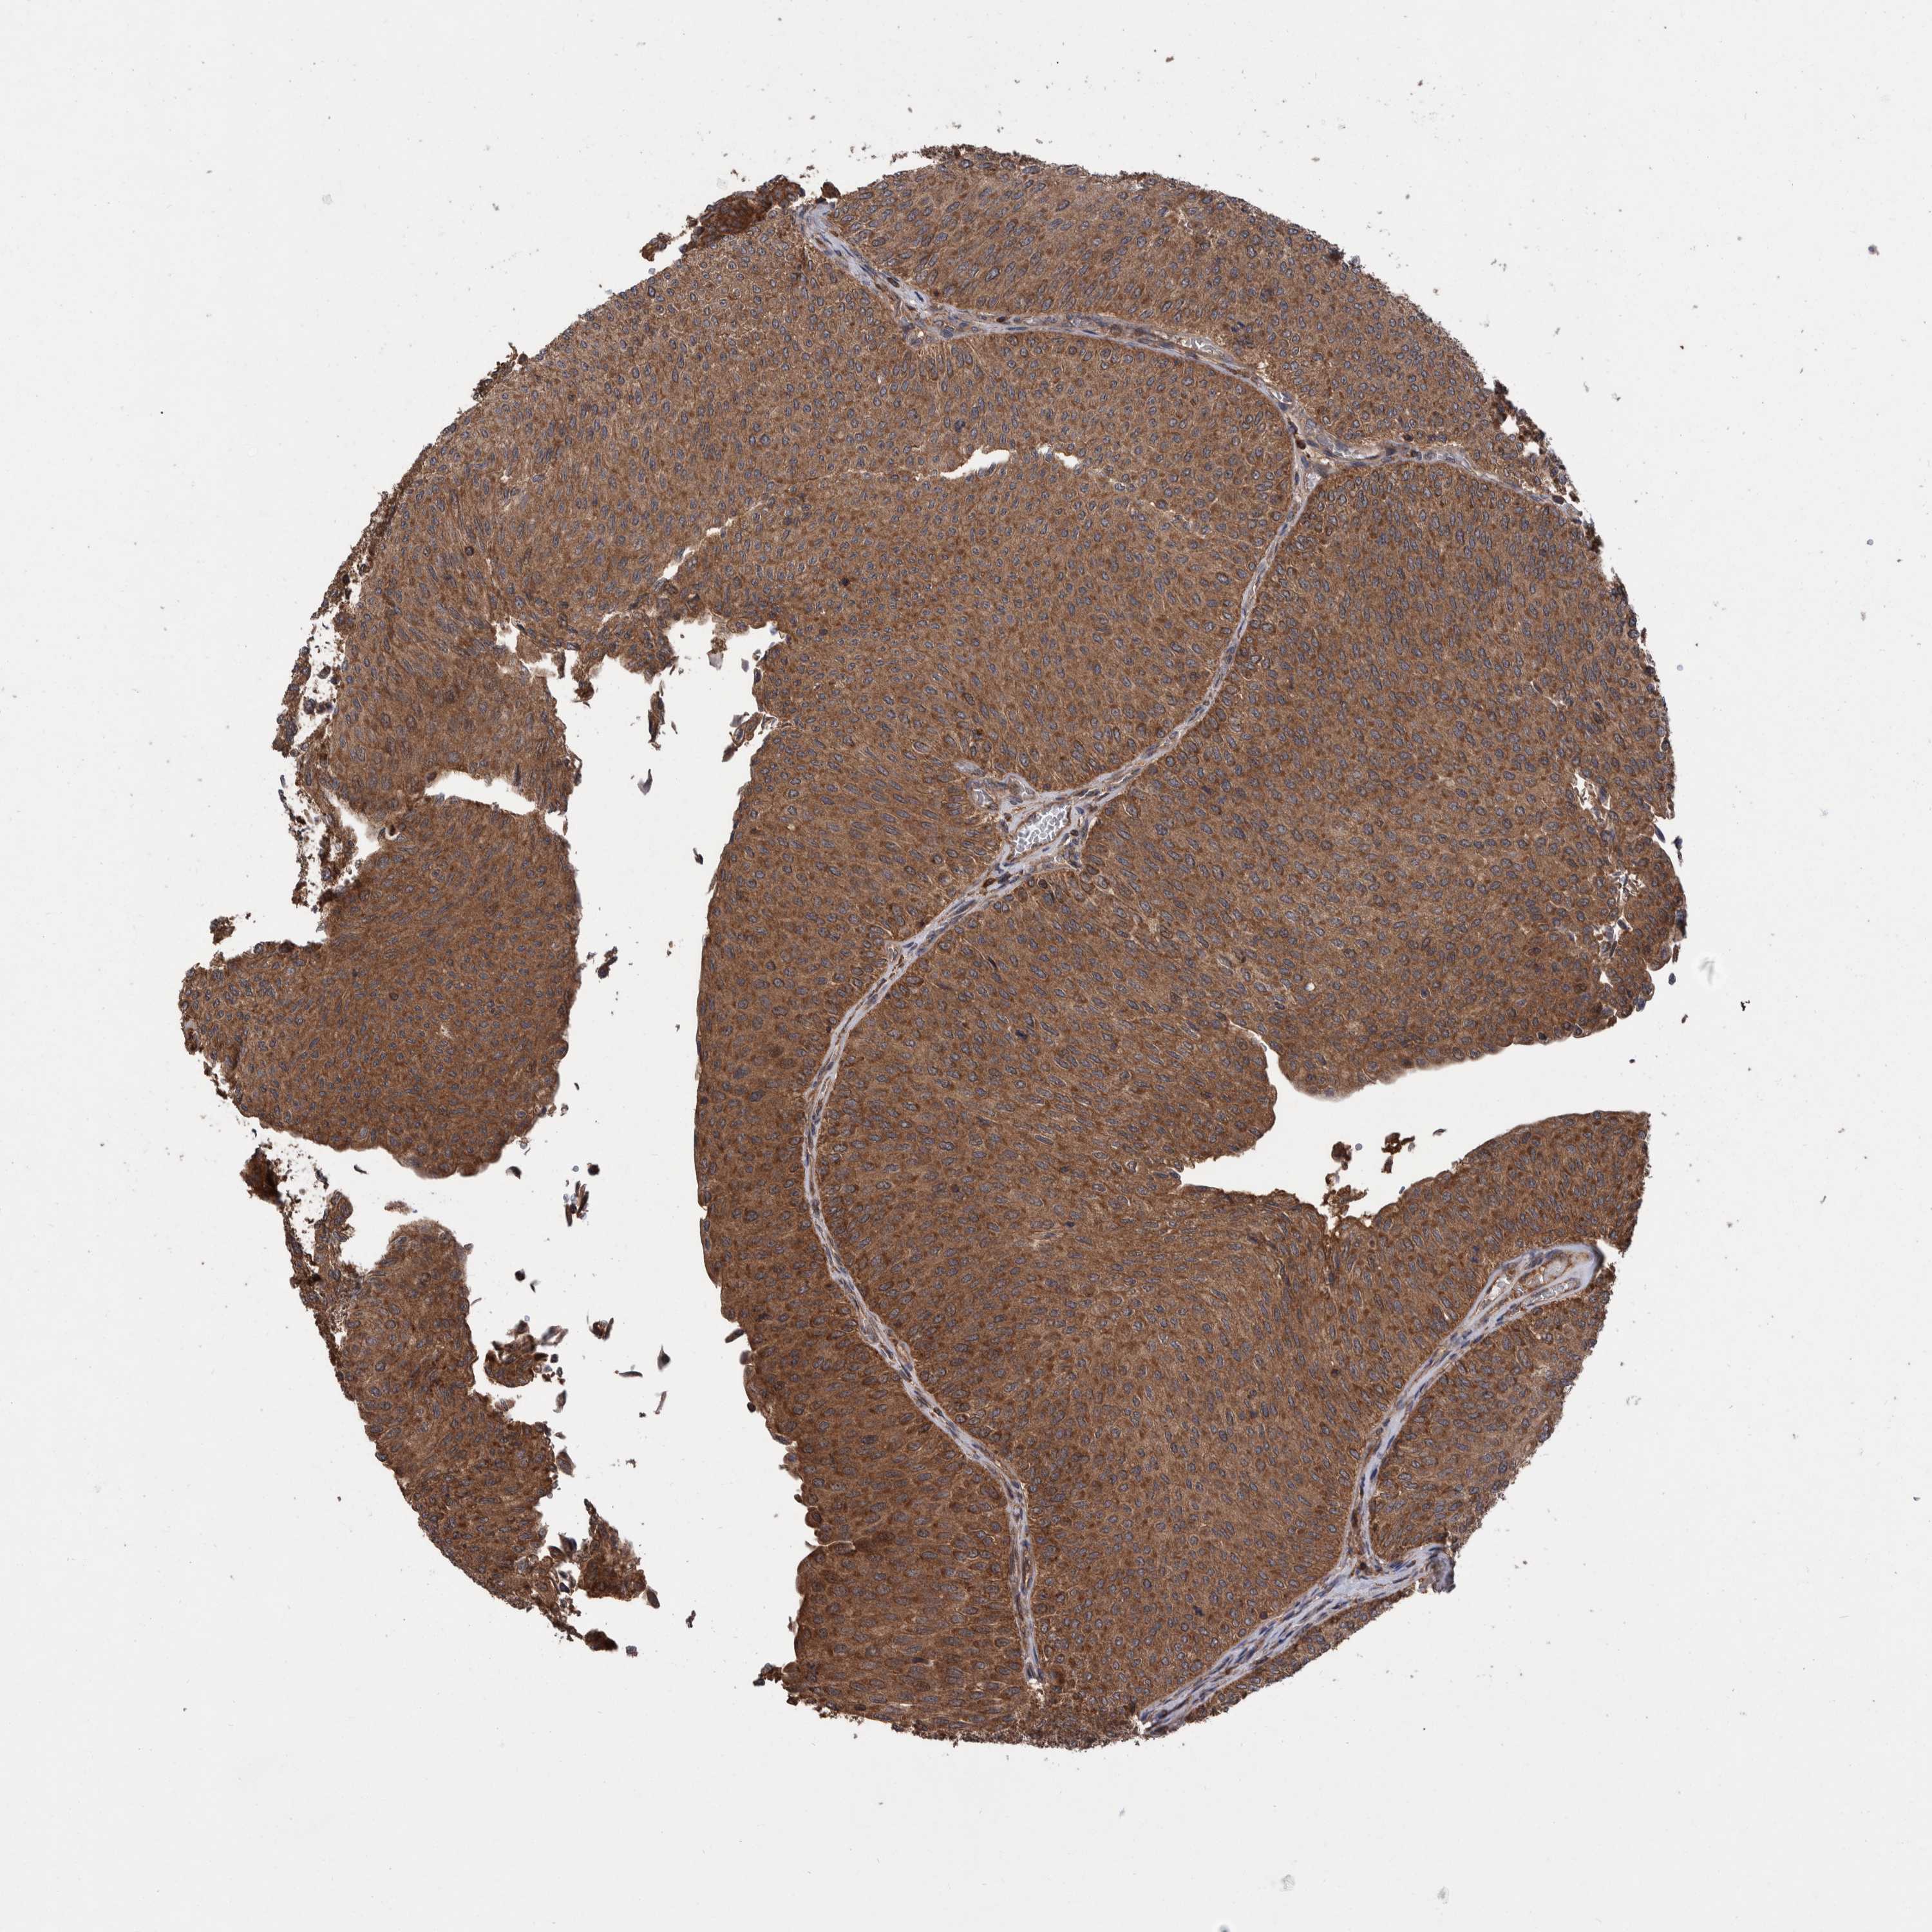

UROTHELIAL CANCER - Protein expressioni

A mouse-over function shows sample information and annotation data. Click on an image to view it in a full screen mode. Samples can be filtered based on level of antibody staining by selecting one or several of the following categories: high, medium, low and not detected. The assay and annotation is described here.

Note that samples used for immunohistochemistry by the Human Protein Atlas do not correspond to samples in the TCGA dataset.

Antibody stainingi

Antibody staining in the annotated cell types in the current human tissue is reported as not detected, low, medium, or high, based on conventional immunohistochemistry profiling in selected tissues. This score is based on the combination of the staining intensity and fraction of stained cells.

Each image is clickable and will lead to virtual microscopy that enables deeper exploration of all samples and also displays staining intensity scores, fraction scores and subcellular localization as well as patient and tissue information for each sample.

Antibody HPA023230

Antibody CAB006260

Urothelial carcinoma, Low grade

Urothelial carcinoma, High grade